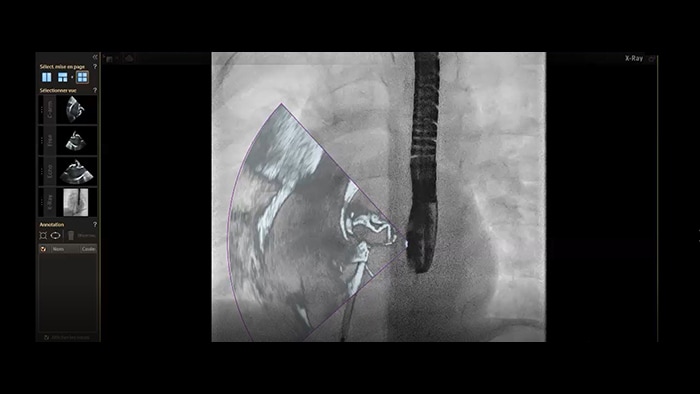

Zamknięcie ASD — łączenie obrazów w czasie rzeczywistym w systemie EchoNavigator

Segmentacja modelu serca w systemie EchoNavigator